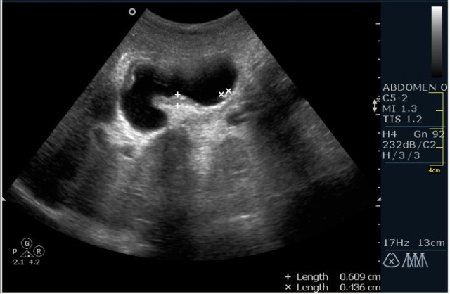

Мужчина 42 года; жалобы на периодические боли в эпигастрии. УЗИ области жёлчного пузыря выявило интересную картину; наблюдается фокальное утолщение стенок пузыря в области тела. Интересно узнать Ваше мнение?

В Желчном пузыре определялся мелкий конкремент и диффузное равномерное гипоэхогенное утолщение стенки на отграниченном участке, заключение морфологов-воспaлительный процесс (признаки холецистита).

Мне интерено, а почему Вы решили что это аденомиоматоз? На представленных сонограммах нет признаков этого заболевания, за исключением фокального утолщения стенки (что крайне не специфично, см. ниже). Если мы не находим пристеночных синусов (Ашоф -Ракитанского) образующихся за счёт неравномерной гиперплазии эпителия ЖП с протрузией эпителия в стенку, и не видим гиперэхогенные фокусы в стенке за счёт кристаллов холестерола; мы не можем выставлять диагноз аденомиоматоз. В нашем случае мы имеем дело с равномерным гипоэхогенным утолщением (см. сонограммы призведённые линейным датчиком с высоким разрешением).